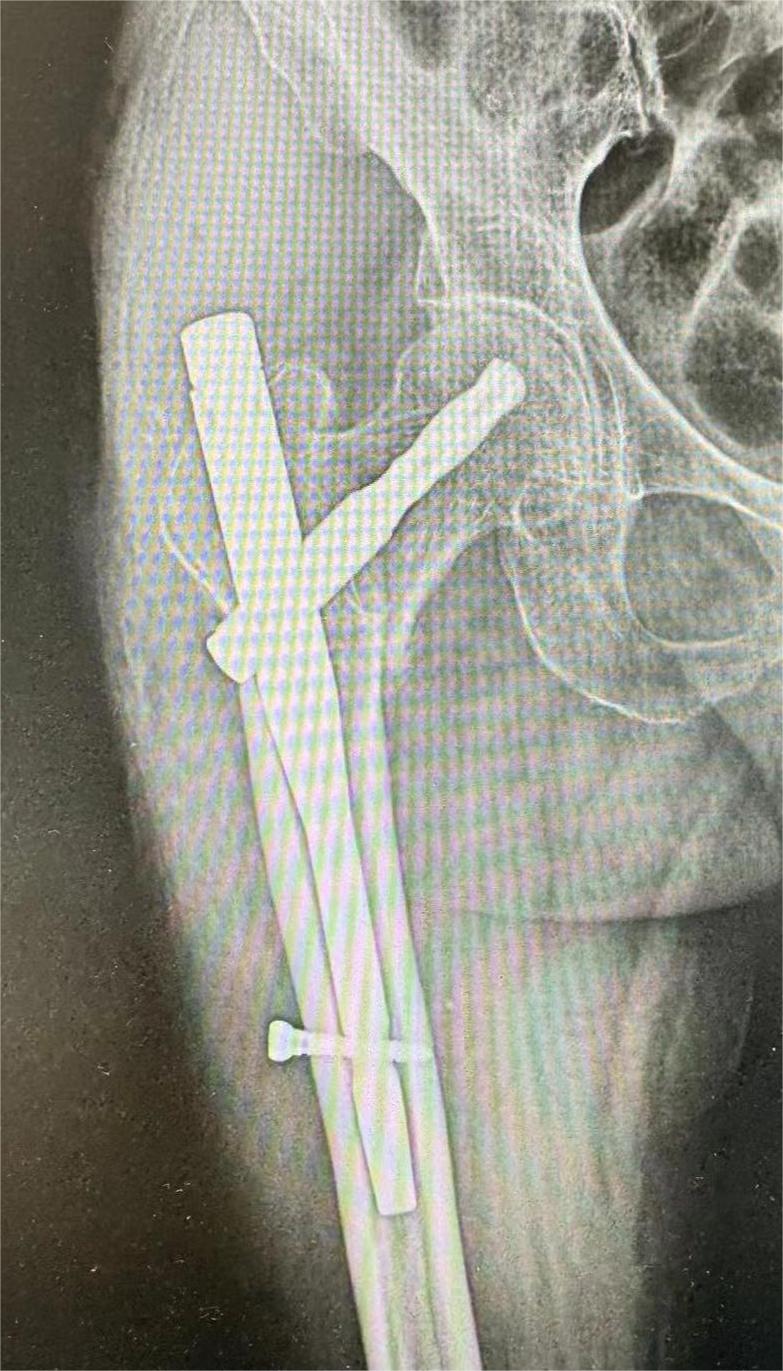

入院后,经过进一步检查,王奶奶还患有慢阻肺、心脏病、高血压等疾病,手术风险较大,若不进行手术,长期卧床保守治疗又会引发肺部感染、下肢静脉血栓、压疮等危及生命。经过科室会诊讨论,决定为王奶奶实施髋部骨折闭合复位内固定手术,以最大限度地恢复王奶奶的关节功能,减少长期卧床带来的风险。

手术前,科室全面评估了王奶奶的整体健康状况,制定了详细的治疗方案,骨科与麻醉手术科紧密合作,为王奶奶量身制定了围手术期的治疗流程和路径,确保手术的安全性和患者的康复效果。手术过程中各项生命体征都非常平稳,在多学科的共同配合下,手术仅用时不到一个小时便顺利完成。术后,科室根据王奶奶的情况制定了个性化的康复方案,通过专业的康复措施有效减轻了患者疼痛,预防并发症发生,术后第二天王奶奶便在家属的协助下下床进行部分负重行走。经过八天的精心治疗,王奶奶切口愈合良好,各项生理指标正常,顺利出院。